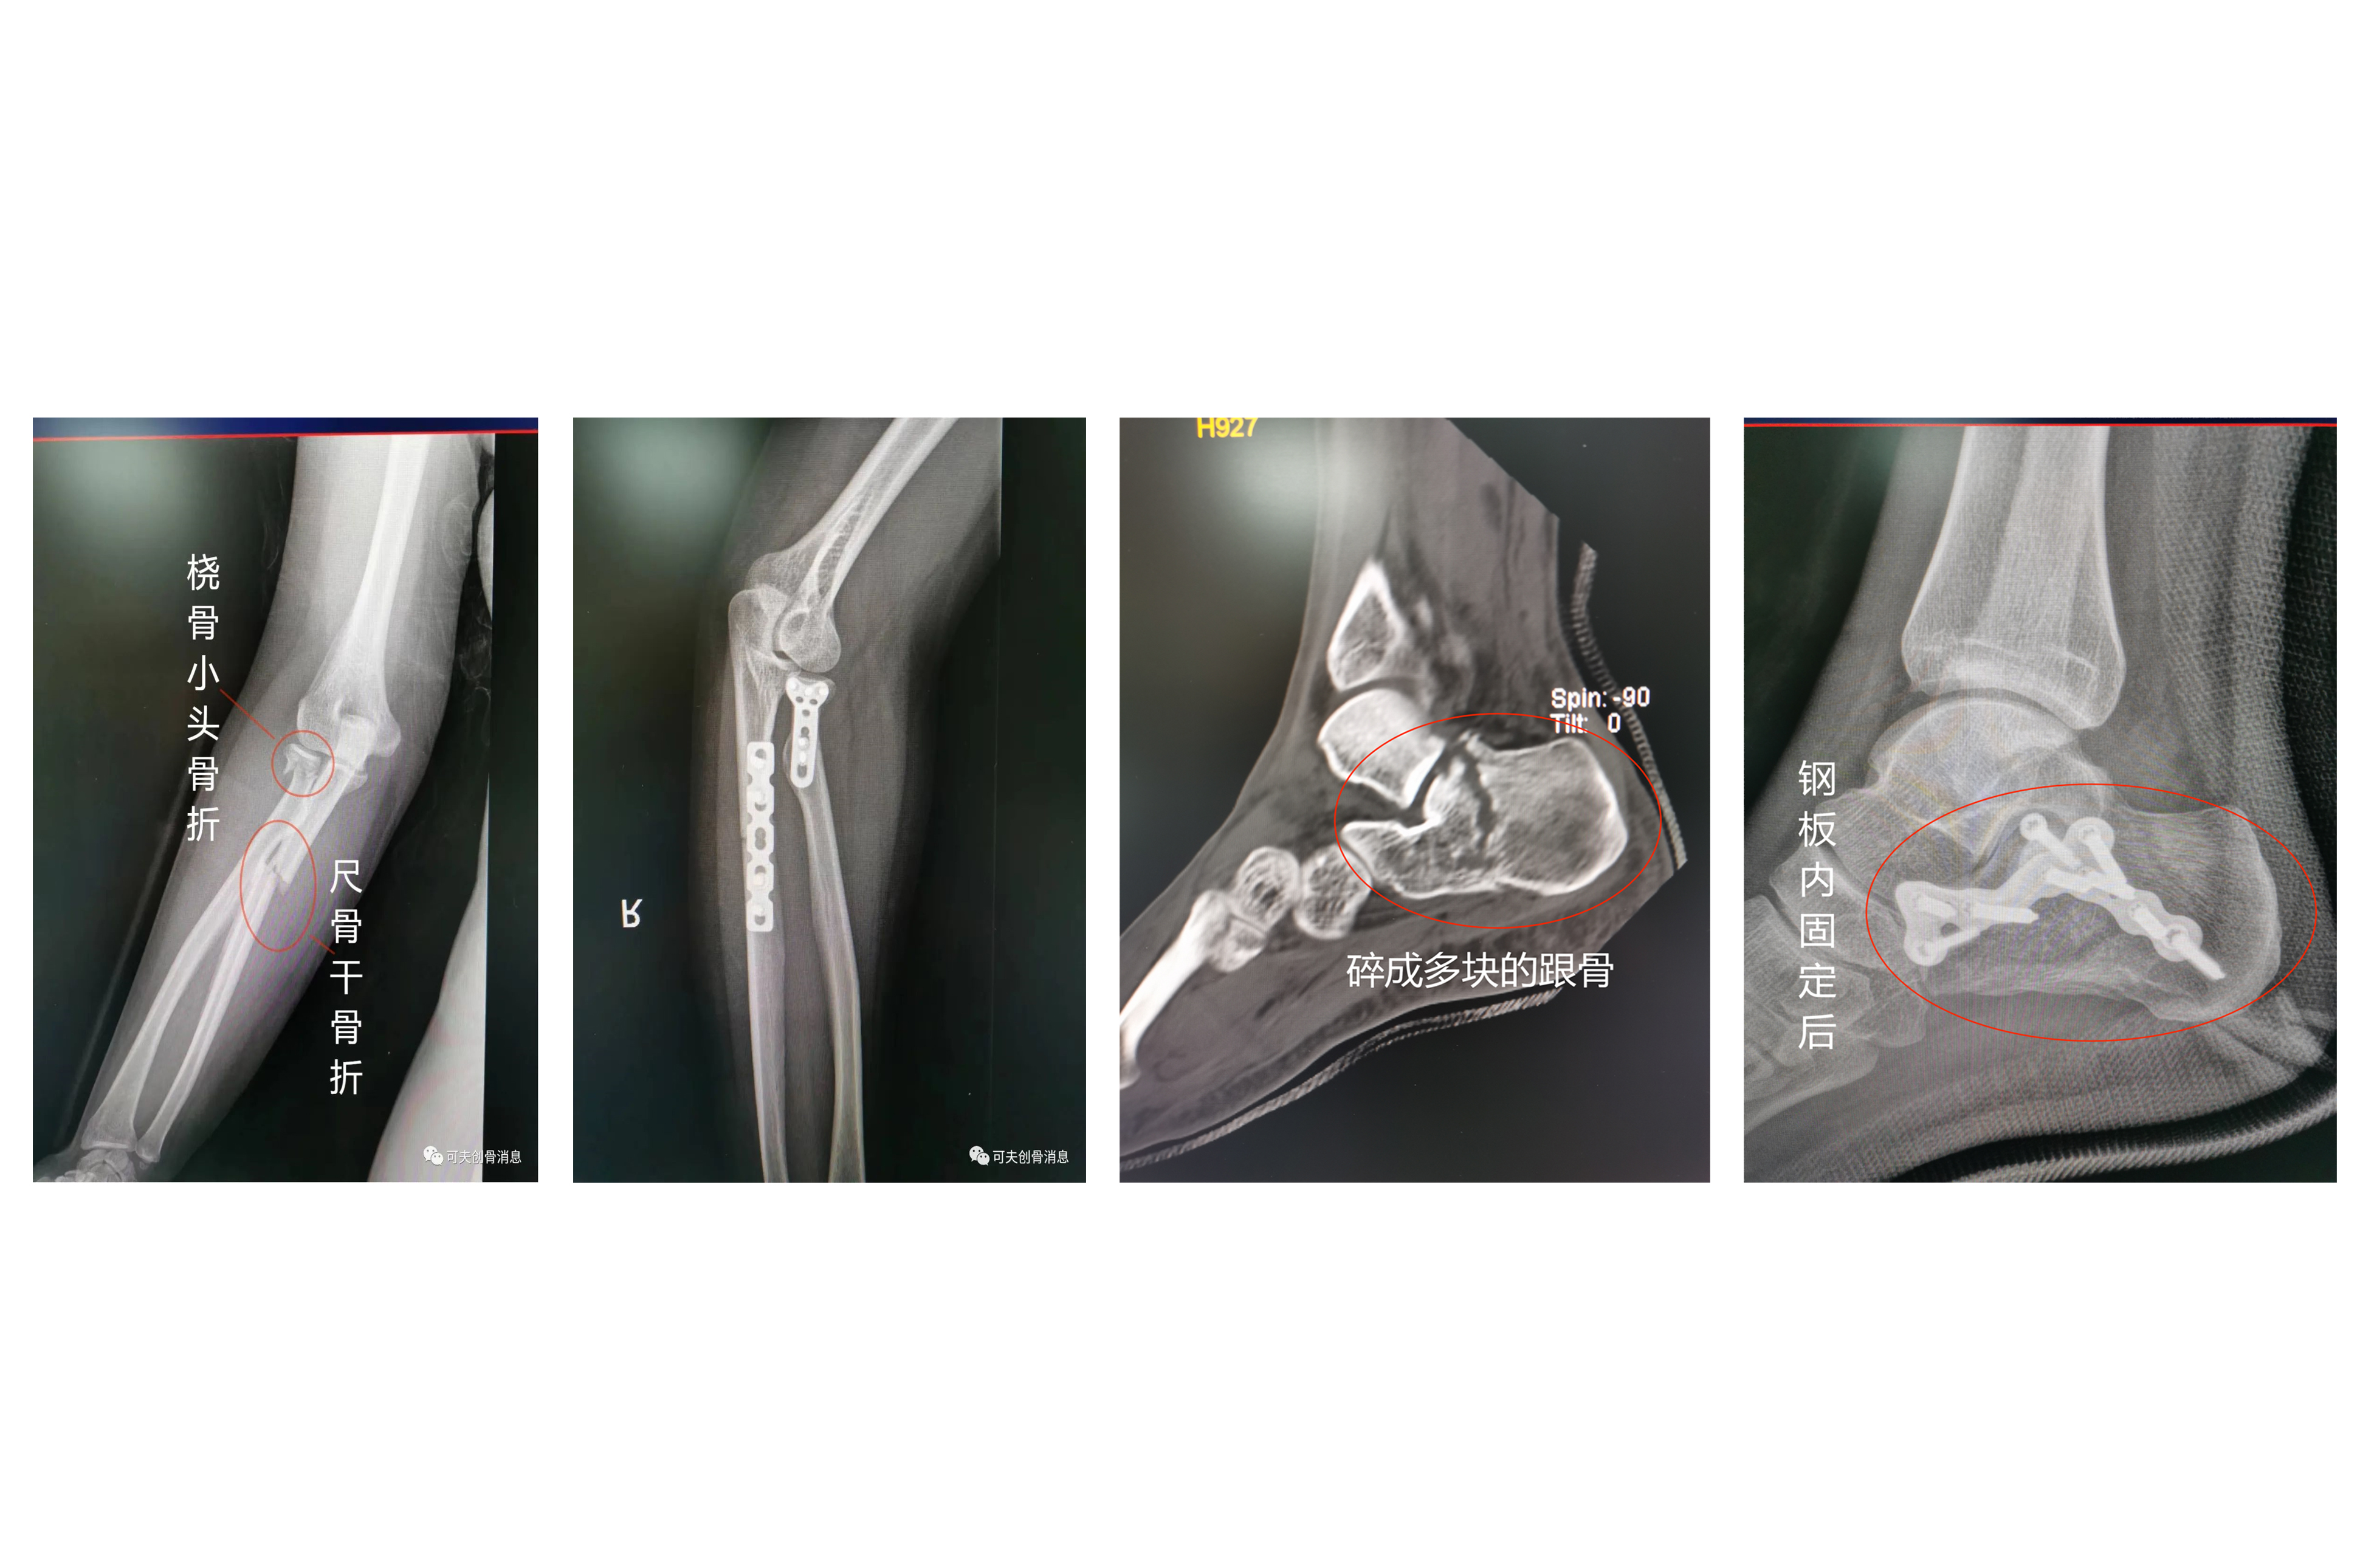

禅医创伤骨科全体人员齐心协力、励志创新,医疗技术特色突出,在严重创伤的急、危、重症救治方面积累了丰富的经验,以股骨粗隆间骨折、骨盆髋臼骨折、四肢骨折、老年骨折、关节损伤、关节炎及各类创伤的诊治为主要特色。我院创伤骨科开展微创治疗老年人股骨粗隆间骨折已有十余年历史,以最小的创伤、最好的疗效、最大的安全系数深得广大老年患者的信赖。我科现有医护团队25人,对术后患者采用中西医结合的康复理疗方式,为患者制定详细科学的康复计划,深受广大患者的好评!